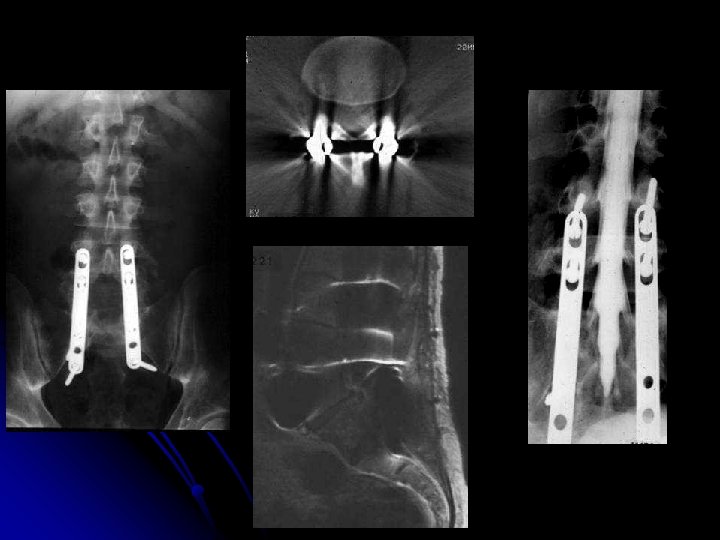

Malformations, scoliose l RX standards (2 segments au moins, cervicale+dorsale ou dorsale+lombaire, ou colonne totale); mesure des angles de scoliose l l Clichés dynamiques: l stabilité ou fixité d'une scoliose, l stabilité ou fixité d'une hypercyphose ou d'une hyperlordose IRM: l malformation de Chiari, l hydromyélie, l moelle attachée, l lipome sacro-coccygien, l méningocèle CT: l malformations vertébrales complexes, diastématomyélie l contrôle post-opératoire (éléments métalliques empêchant la réalisation d'une IRM) Échographie (petits enfants): défauts de fermeture de l'arc postérieur et moelle attachée